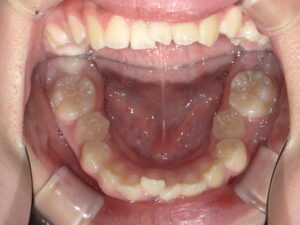

今回の症例の初診時の年齢は12歳1か月で、永久歯への生え変わりがほぼ完了しつつある時期でした。上下顎ともに歯並びのデコボコ・ガタつきが強く、横顔を確認すると出っ歯(上下顎前突)の傾向が認められました。さらに噛み合わせが深く、上下の正中にもずれが見られました。

<初診時>

<下顎>